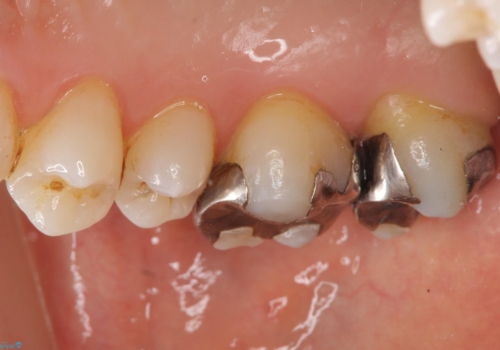

- 銀歯を白くしたいとのことで来院されました。

銀の詰め物を除去した後、その奥にある古い詰め物も除去し完全にむし歯を取り切ったことを確認してからセラミッククラウンを装着していきます。